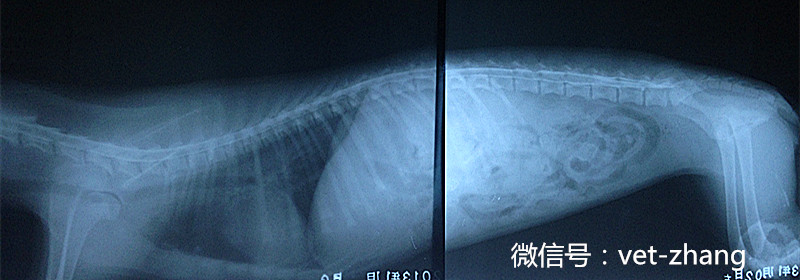

此图为延髓池注入造影剂后,把犬放置在斜面上,保持头高尾低姿势5min后拍摄的右侧为片

此图为延髓池注入造影剂后,把犬放置在斜面上,保持头高尾低姿势8min后拍摄的右侧为片